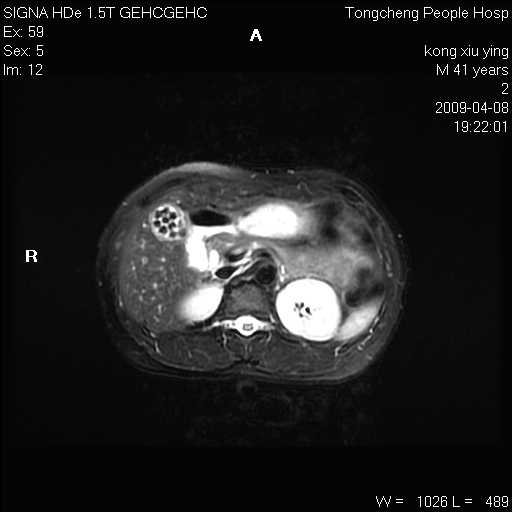

标题: CL1008:【经典】胆囊石榴籽样结石。 [打印本页]

标题: CL1008:【经典】胆囊石榴籽样结石。

女,41岁。健康体检——彩超提示:胆囊显示不清。平素健康,无不适感。

腹部mr扫描及mrcp,图像如下: